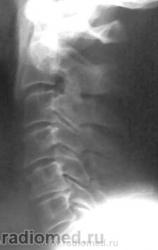

Остеохондроз, спондиллоартроз, протрузия МПД С5-С6 кзади. Что Вас смущает на этих снимках? Игра теней на уровне С6(прямой снимок)?

Согласен с О.Д. А прямые снимки можно делать лежа с отклонением центр. луча под углом 15 град. краниально, центровать также, на щитовидный хрящ, очень будет красиво. Можно даже стоя, но не у всех аппаратов в вертикальном положении угломер работает.

На теле С5 вероятно изображение унко-вертебрального артроза. Это его законное место. В прямой проекции вообще толком ничего не видно. Снимки очень неважные. Почему ваши лаборанты так широко раскрыли диафрагму? Качество очень страдает. Если есть сомнения в бабочковидном позвонке, можно сделать прямую томограмму.

По данным снимкам сие недоказуемо. Надо делать лин. томографию.